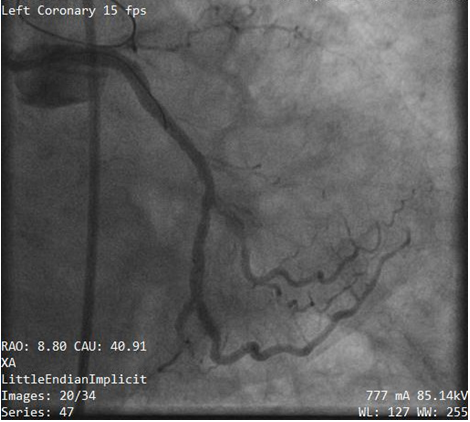

A 65- year old female with an underlying disease of hypertension, severe mitral valve regurgitation with history of mitral valve repair operation for over 8 years ago complained of stable angina CCS (Canadian cardiovascular society angina grade) class 3 for 2 months. She also had a past history of coronary angioplasty and one drug eluting stents (DES) were placed in right coronary artery (RCA). Her coronary angiogram show chronic total occlusion at left anterior descending (LAD) artery and significant bifurcation lesion at distal left circumflex (LCX) artery (Figure 1). The patient declined surgical intervention. Considering her decision and symptoms percutaneous coronary intervention (PCI) was planned after an informed consent.

Figure 1 Initial coronary angiogram of left coronary artery show significant lesion at bifurcation of left circumflex artery (LCX) and obtuse marginal 2(OM2) branch.